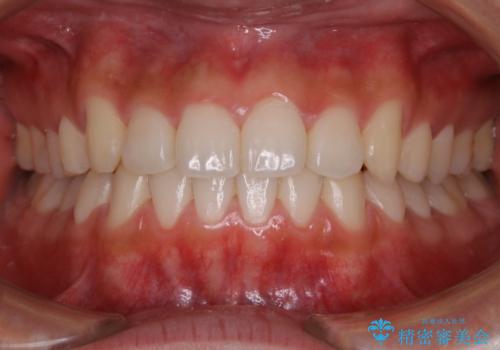

[ 前歯のねじれ・がたつき ] マウスピース矯正

![[ 前歯のねじれ・がたつき ] マウスピース矯正の症例 治療前](https://seimitsushinbi.jp/wp/wp-content/uploads/2024/02/4007c6479f6bce11863dcdd32ed5e39b-500x350.jpg?v=1708502552)

![[ 前歯のねじれ・がたつき ] マウスピース矯正の症例 治療後](https://seimitsushinbi.jp/wp/wp-content/uploads/2024/02/e7a01485e4f4dd0da04705fde4cc34cc-500x350.jpg?v=1708502585)